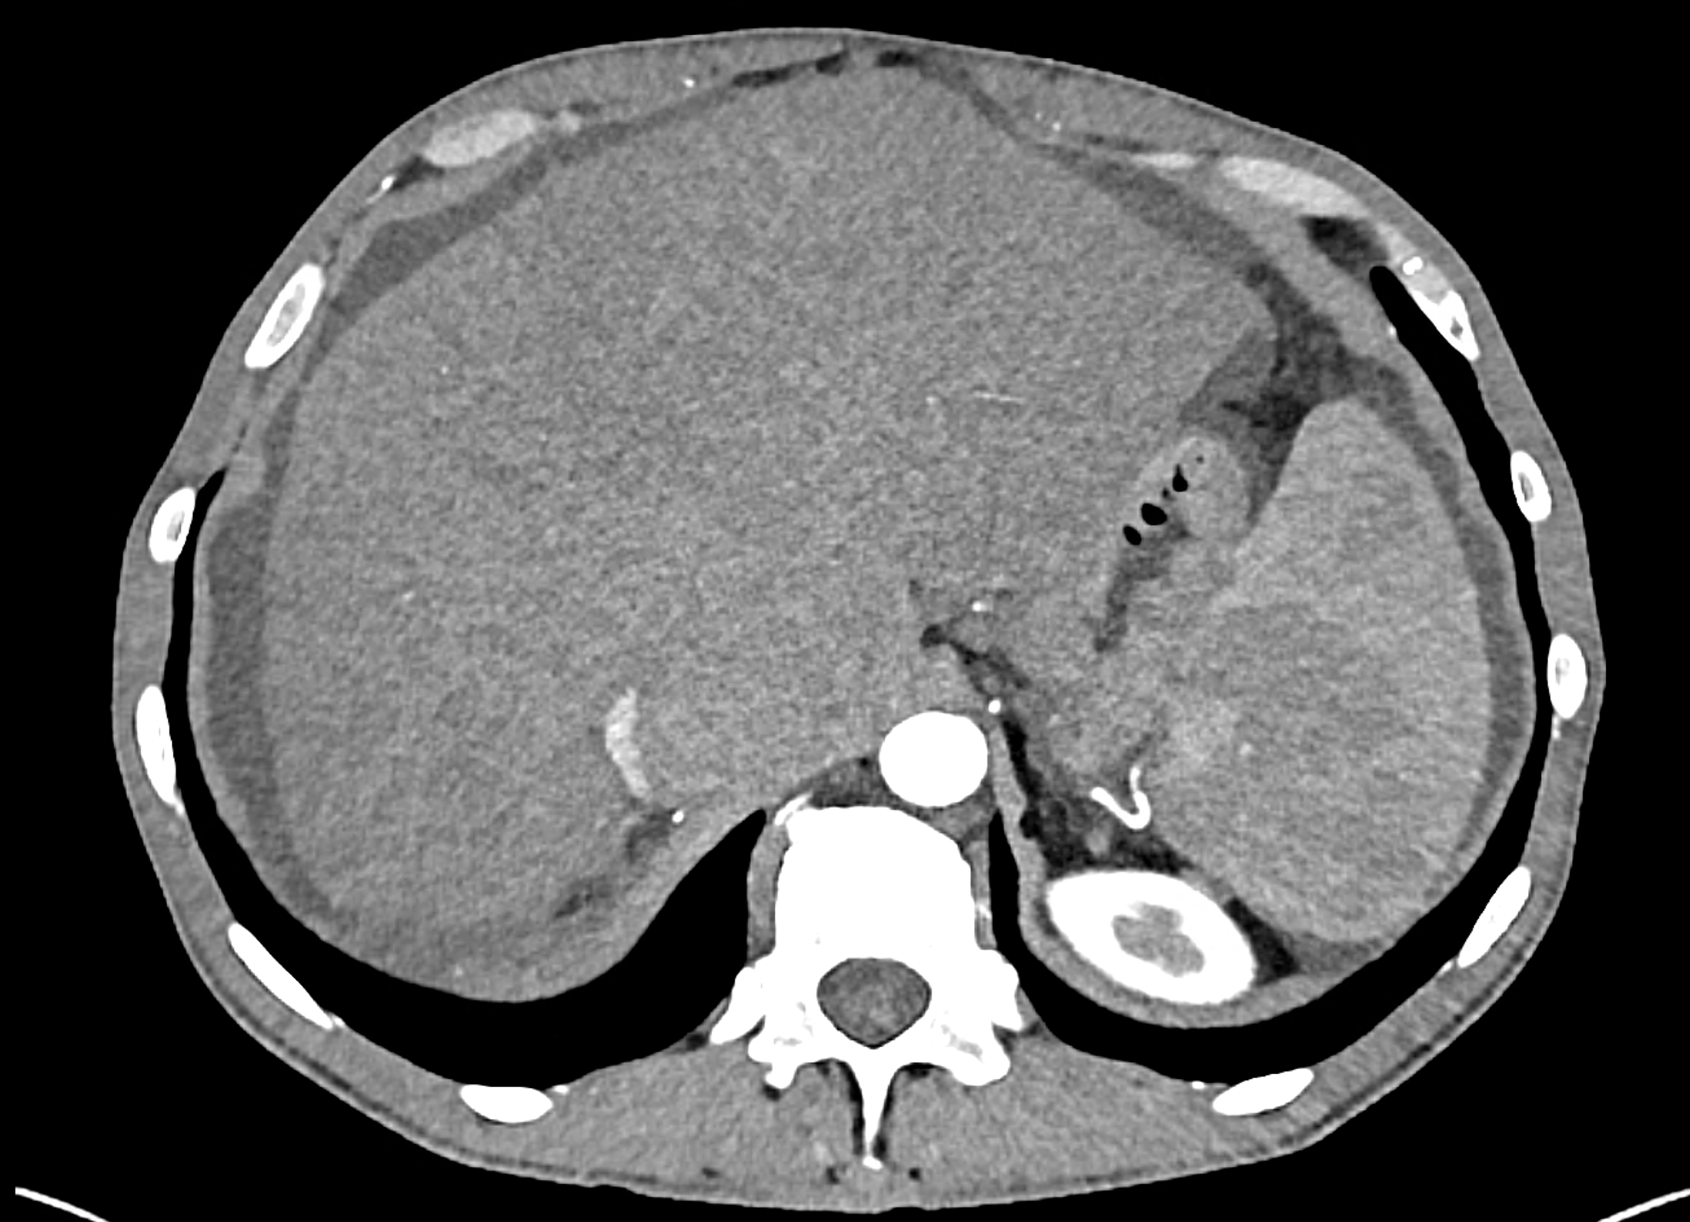

In CT images, BCS manifests as non-homogeneous enhancement of liver tissue in the arterial and especially in the portal phase, although in the portal phase may be increased, especially in the caudate lobe and left lobe, which are often hypertrophic (the hypertrophy and the enhancement is caused due to the possibility of the venous drainage directly into the inferior vena cava through the direct caudate veins), in contrast to the reduction in the right lobe. The portal vein is free, whereas even in the late phase, the hepatic veins and their contrast filling are not visible. Thrombotic occluded veins are hypodense.

A patient in his sixties with a Leiden mutation of factor V and a heterozygous prothrombin mutation presents with abdominal pain. Ultrasound examination reveals ascites and enlargement of the liver.There is enlargement of the liver, particularly the left lobe and caudate lobe. The hepatic veins are centrally filled with contrast medium due to reflux at the confluence with the inferior vena cava, and their radicular parts are thrombosed. There is typical chronic liver remodelling and the formation of centrifugal collateral circulation, including esophageal varices, and ascites is present in the abdominal cavity.

the axial images in the arterial, and the portal phases